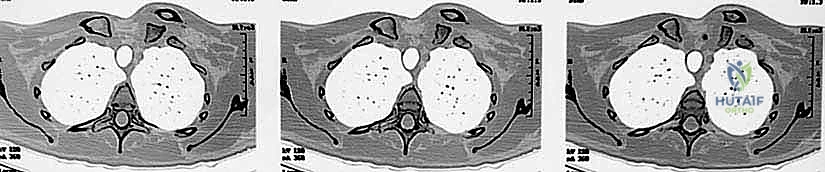

- التصوير المقطعي المحوسب (CT Scan) - المعيار الذهبي: يؤكد الدكتور هطيف أن الأشعة المقطعية، خاصة مع إعادة البناء ثلاثي الأبعاد (3D Reconstruction)، هي الإجراء الحاسم. فهي تحدد بدقة متناهية اتجاه الخلع، وجود كسور مصاحبة، ومدى قرب الترقوة من الهياكل الحيوية.